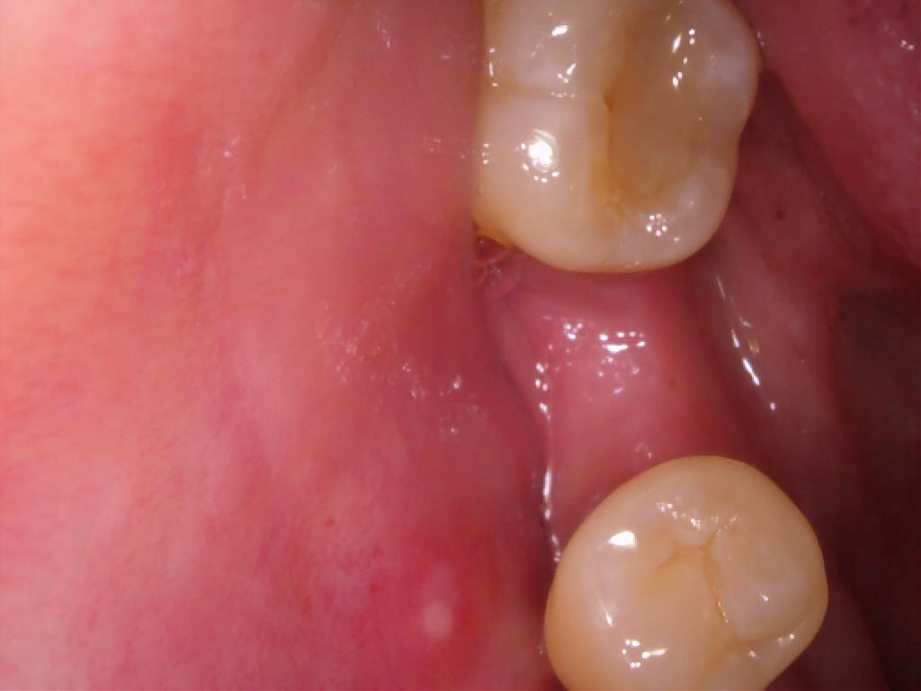

治療前

治療後

レントゲン写真

- 治療名称

- 右下56番パーシャルデンチャー部のインプラント治療

- 患者の症状

- 右下56番にパーシャルデンチャーを装着しており機能及び審美的に問題を抱えている。

- 治療内容

- まず、CT撮影による精密な骨の分析・治療計画を立てガイドを使いインプラント埋入しインプラントが骨と結合するのを待つ間に仮の歯を入れます。その後本歯を作成して装着しました。

- 治療期間・回数

- インプラント埋入からジルコニアセットまで三か月半

- 費用

※自由診療となります - ■総額:¥660,000(税込み) ■内訳:埋入(ガイド込み)¥200,000×2、仮歯¥20,000×2、被せ物¥80,000×2

- リスク・副作用

- ・術後の腫れ・痛み・出血 ・感染(インプラント周囲炎) ・インプラントの脱落 ・神経損傷によるしびれ ・破損・ゆるみ